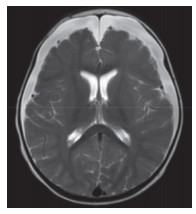

入院第2天(病程第6天)患儿双足及肛周出现散在红色斑疹。入院第7天双手、双足出现多处指甲与皮肤移行处脱皮,符合典型川崎病的诊断标准。分别于病程2~4 d(外院)和7~8 d进行2个疗程的丙种球蛋白(2 g/kg)治疗,发热无好转,外周血白细胞(19.06~24.80)×109/L;2次应用丙种球蛋白后C反应蛋白均出现一过性下降:第1次从 > 210.0 mg/L降至69.6 mg/L,第2次从56.3 mg/L降至28.0 mg/L,但3 d内再次升高至75.7 mg/L。铁蛋白7 d内逐步降至正常。入院第8天诊断为丙种球蛋白不反应型川崎病,加用静脉糖皮质激素[2 mg/(kg·d),共7 d],用药当日体温平稳,之后未再发热,外周血白细胞及C反应蛋白在使用激素后1周内逐步降至正常。入院第10天,头部MRI检查结果显示双侧额颞部硬膜下积液(图 3)。复查腰椎穿刺,脑脊液压力13 cmH2O。脑脊液常规检查:白细胞10×106/L,中性粒细胞百分比50%,单个核细胞50%。脑脊液生化检查:血糖3.93 mmol/L,蛋白1.14 g/L。1周后复查头部CT显示硬膜下积液无明显改变(图 4)。

| 图 4 患儿入院第16天头部CT |